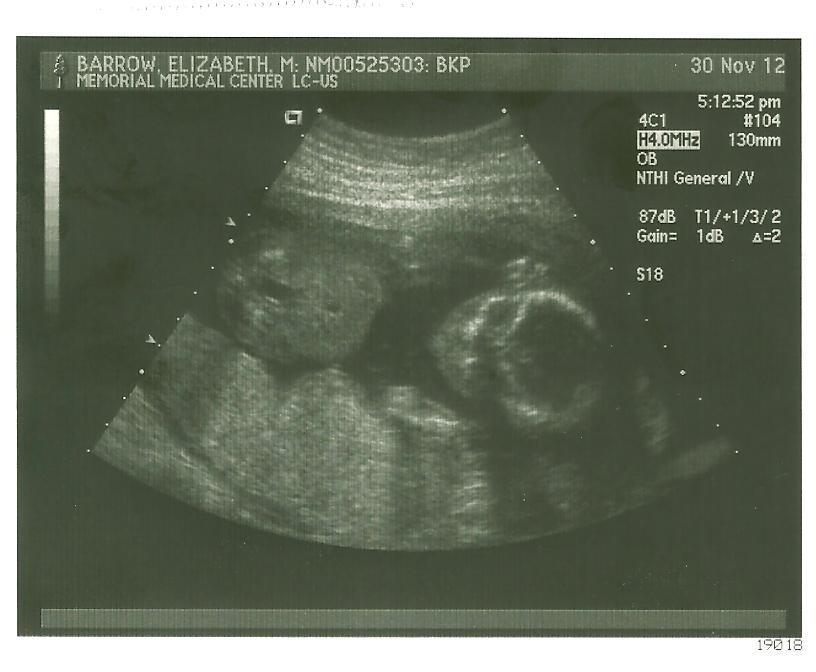

ultrasound1

Ultrasound Time!